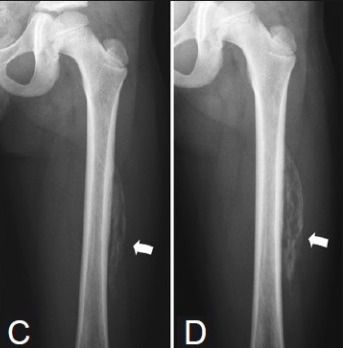

Миозитов ревматических

Миозитов ревматических 114 фотографий